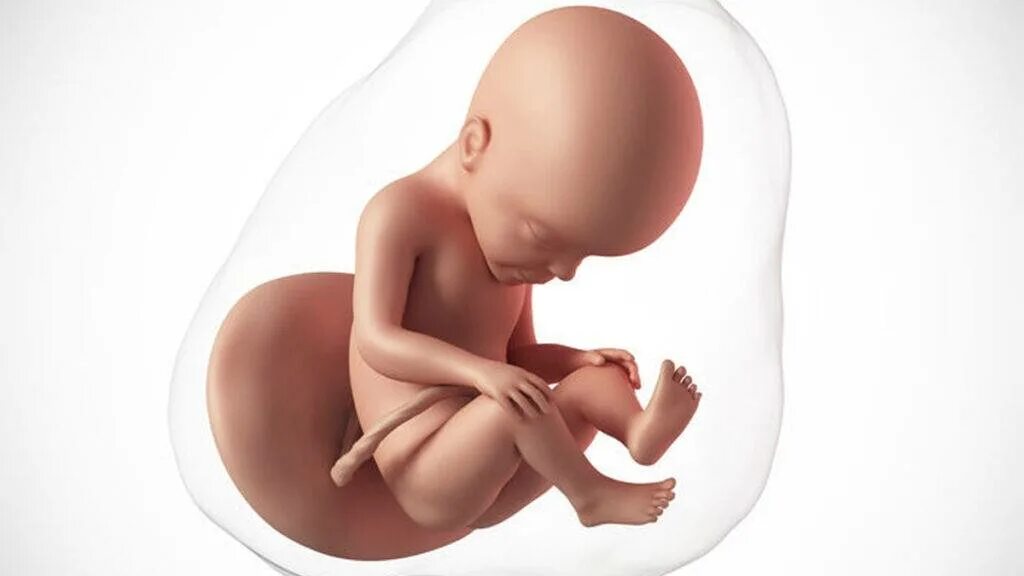

29 недель 4 дня